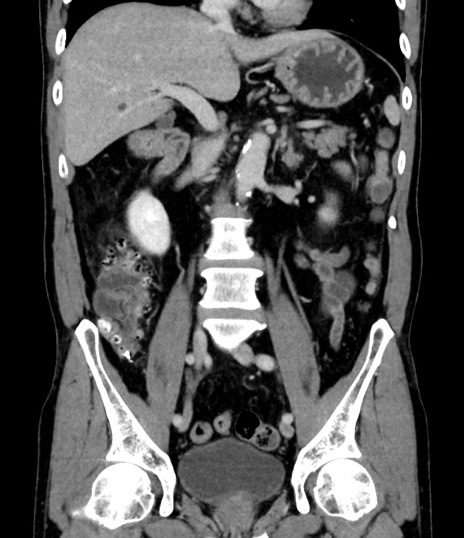

症例8(冠状断像)

【症例】 60歳代男性

【主訴】 黒色吐物

【現病歴】 4日前から嘔気自覚、2日前の朝食後にも嘔気あり、自分で手で嘔吐反射起こし嘔吐したところ血が混ざっていたため受診。

【既往歴】 5年前汎発性腹膜炎を伴う急性虫垂炎で手術、高血圧、前立腺肥大症、高脂血症

【身体所見】 腹部正中に手術癩痕あり 腹部平坦・軟圧痛なし膨満感あり

【データ】WBC 8400、CRP 4.54